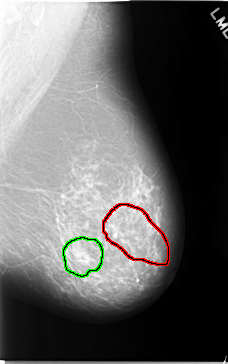

C_0044_1.LEFT_MLO

FILE: C_0044_1.LEFT_MLO.OVERLAY

TOTAL_ABNORMALITIES 2

ABNORMALITY 1

LESION_TYPE CALCIFICATION TYPE FINE_LINEAR_BRANCHING DISTRIBUTION SEGMENTAL

ASSESSMENT 5

SUBTLETY 4

PATHOLOGY MALIGNANT

TOTAL_OUTLINES 1

BOUNDARY

ABNORMALITY 2

LESION_TYPE MASS SHAPE OVAL MARGINS OBSCURED

ASSESSMENT 3

SUBTLETY 5

PATHOLOGY BENIGN